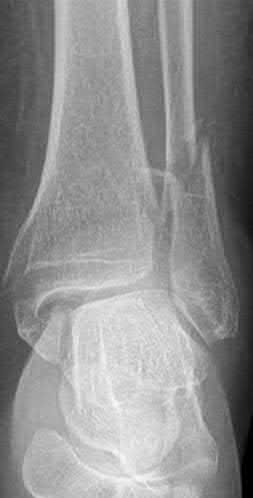

A 28-year-old male sustains a severe hyper-dorsiflexion injury to his ankle in a motor vehicle accident, resulting in a Hawkins Type III talar neck fracture. Which of the following arteries provides the predominant blood supply to the body of the talus, placing it at significant risk for avascular necrosis in this injury?

The artery of the tarsal canal, which is a branch of the posterior tibial artery, provides the dominant blood supply to the talar body. In a Hawkins Type III fracture (talar neck fracture with subtalar and tibiotalar dislocation), the blood supply from the artery of the tarsal canal, the artery of the sinus tarsi, and capsular vessels are disrupted, leading to an avascular necrosis (AVN) rate approaching 100%.